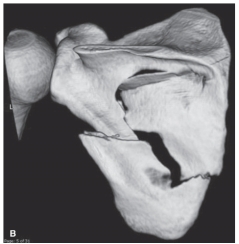

5

-Refer to the figure. Name the imaging modality.

A) MRI

B) Radiograph

C) Arthrogram

D) 3D CT

6

-Refer to the figure. Describe the pathological condition.

A) Osteolytic destruction

B) Degenerative joint disease

C) Fracture of the scapula

D) Dislocation of the glenohumeral joint